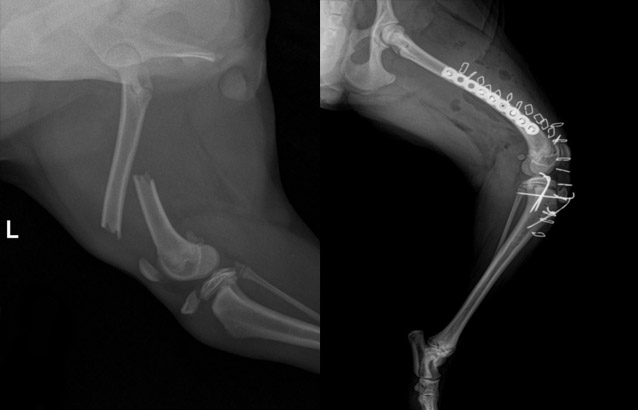

01골절수술

단순골절뿐만 아니라 분쇄골절, 성장판 골절 등 다양한 골절 수술을 진행하며, 수술을 위한 다양한 이식물 적용이 가능합니다.

불유합이 있거나, 노령 등으로 인하여 골유합에 문제가 있을 경우를 대비하여 다양한 골이식재를 적용하여 치료하고 있습니다.

대퇴골 골절 및 경골 성장판 골절 수술 전 / 후